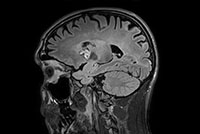

Large lesion brain imaging with synthetic MRI